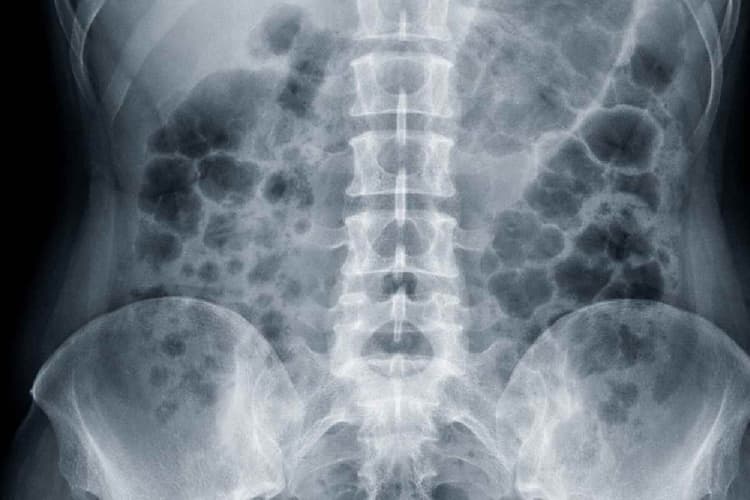

महिला के बेटे ने बताया कि हाल ही में उनकी मां ने एक डॉक्टर से परामर्श लिया जिन्होंने गुर्दे में पथरी होने की आशंका जताई. डॉक्टरों ने एक्स-रे जांच कराने की सलाह दी. शिबिन ने बताया कि एक्स-रे रिपोर्ट में कथित रूप से पेट के भीतर एक ‘आर्टरी फोर्सेप्स’ दिखाई दिया. इसके बाद मेडिकल कॉलेज के डॉक्टरों ने अगले सप्ताह इसे निकालने की पेशकश की.